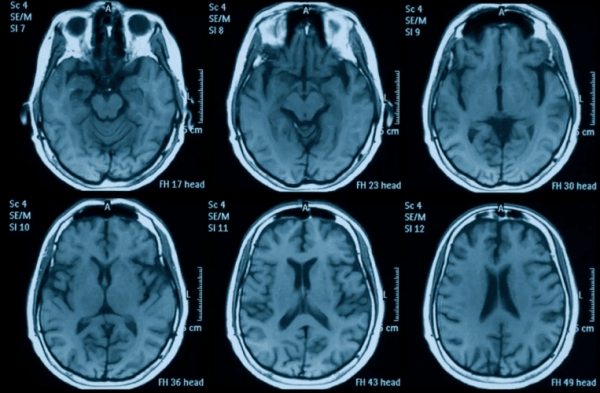

Raziskovalci so uporabili umetno inteligenco, usposobljeno na več kot 15.000 skeniranjih možganov, da bi prepoznali strukturne spremembe, ki jih spremlja staranje. Nato so analizirali dve skupini: kontrolno skupino s posnetki, opravljenimi pred marcem 2020, in eksperimentalno skupino, ki je imela en posnetek pred in enega po začetku »pandemije«.

Spremembe v sivi in beli snovi so bile prisotne tudi pri ljudeh, ki niso nikoli imeli zdravstvenih težav, kar kaže na to, da je »pandemija« sama po sebi kot socialni in psihološki pojav pustila merljiv nevrološki pečat.